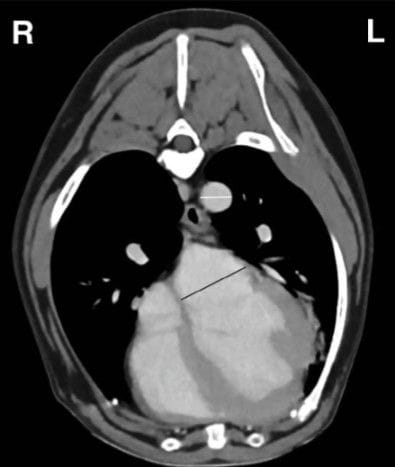

Postcontrast transverse CT image of the thorax at thelevel of the left atrium in a 19.6 kg Beagle dog with left atrial enlargementidentified on 2D echocardiography. The CT left atrium-to-aorta (LA:Ao)measurement technique is demonstrated. The left atrial transverse diam-eter was measured at the point of maximal left atrial width, not includingthe pulmonary veins or left auricle (solid line, 19.9 mm). The short-axisaortic diameter was measured (dashed line, 8.8 mm). The CT LA:Ao ratioin this dog was 2.3